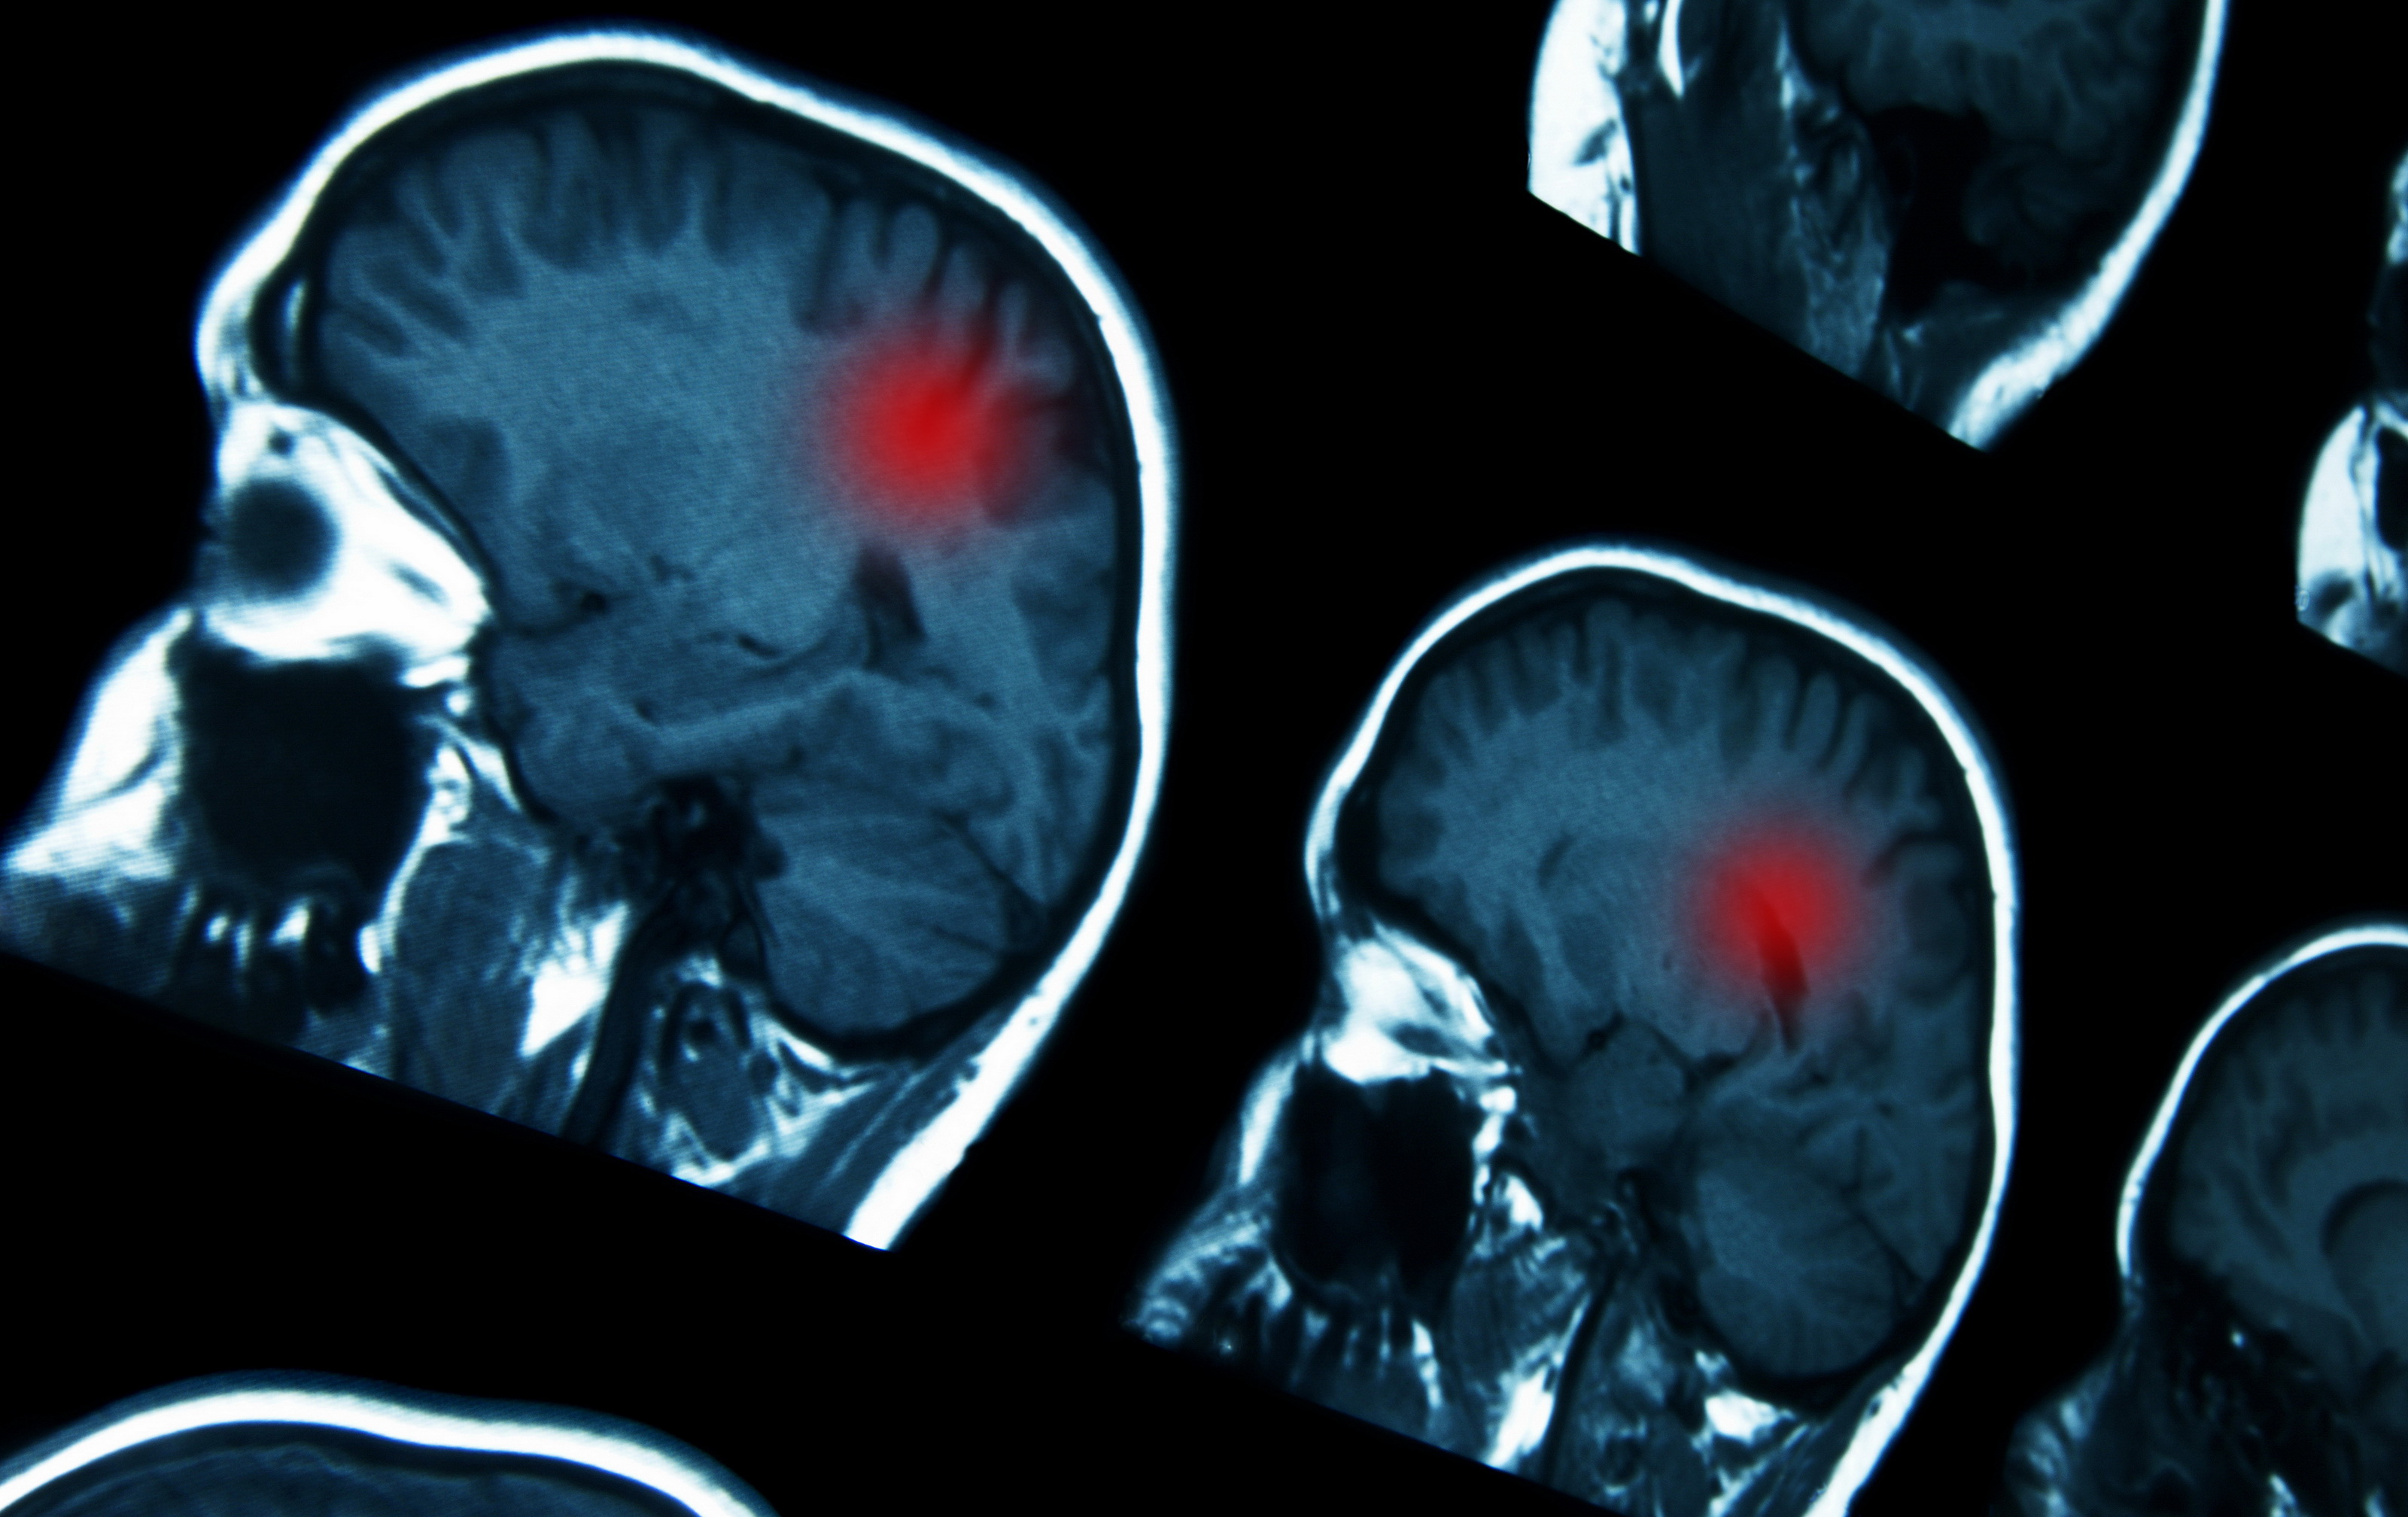

Guz mozgu. Guzem mózgu nazywa się nie tylko nowotwór, ale także każdą inną obcą dla mózgu strukturę, której powstanie i rozwój powoduje wzrost ciasnoty śródczaszkowej Najczęstszymi guzami mózgu jest ropień mózgu, tętniak, pasożyt lub torbiel pajęczynówki Występujące objawy spowodowane są wzmożonym ciśnieniem śródczaszkowym i ogniskowym. Guzy mózgu mogą być zmianami pierwotnymi bądź wtórnymi Pierwotny guz mózgu rozwija się w tkance mózgowej i rzadko stanowi źródło przerzutów do innych lokalizacji Znacznie częstszą postacią są wtórne guzy mózgu, stanowiące przerzuty innych nowotworów, takich jak czerniak, rak płuc, rak piersi i rak nerki. A brain tumor occurs when abnormal cells form within the brain There are two main types of tumors cancerous (malignant) tumors and benign (noncancerous) tumors Cancerous tumors can be divided into primary tumors, which start within the brain, and secondary tumors, which most commonly have spread from tumors located outside the brain, known as brain metastasis tumors.

Objawy jakie daje guz pnia mózgu mogą być silnie urozmaicone i uzależnione od jego utkania, dokładnej lokalizacji oraz rodzaju wzrostu Dane statystyczne pokazują, że około 25% zmian w pniu mózgu to guzy ograniczone, pozostałe wzrastają w sposób określany jako rozlany. GUZ MÓZGU U PSA!. Przez guz mózgu rozumiemy obce dla mózgu struktury, których wzrost powoduje zwiększenie ciśnienia wewnątrzczaszkowego Rozróżniamy guzy pierwotne i przerzutowe Co roku 6 osób na 100 000 dowiaduje się o pierwotnym nowotworze mózgu Średnio 1 na 12 przypadków występuje u dzieci poniżej 15 roku życia.

Rak mózgu (Guz) Nowotwory ośrodkowego układu nerwowego (OUN) to procesy rozrostowe, powodujące ucisk wewnątrz czaszki oraz (znacznie rzadziej) w kanale kręgowym Używa się zamiennie określenia guz, chociaż o guzie można też mówić w przypadku obecności ropni, krwiaków i pasożytów w OUN. Chłoniak mózgu zaliczany jest do grupy chłoniaków ośrodkowego układu nerwowego (OUN) Stanowi rzadko występującą przypadłość Może występować jako zmiana pierwotna i stan ten określa się mianem pierwotny chłoniak mózgu lub w przebiegu rozsianego procesu nowotworowego i wówczas chłoniak jest przerzutem do mózgu. Przez guz mózgu rozumiemy obce dla mózgu struktury, których wzrost powoduje zwiększenie ciśnienia wewnątrzczaszkowego Rozróżniamy guzy pierwotne i przerzutowe Co roku 6 osób na 100 000 dowiaduje się o pierwotnym nowotworze mózgu Średnio 1 na 12 przypadków występuje u dzieci poniżej 15 roku życia.